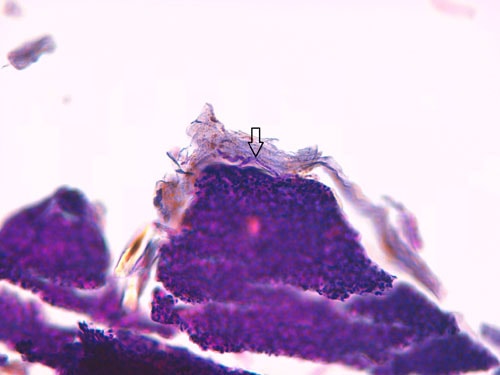

- les biopsies cutanées (LAPVSO) montrent également des vésiculo-pustules contenant des cellules acantholytiques, ainsi que des éléments PAS-positifs au sein des croûtes, évoquant fortement des hyphes mycéliennes (Photos 6 à 8).

Biopsie d’une lésion pustuleuse du pavillon auriculaire (X40, LAPVSO) Visualisation de cellules acantholytiques (X400, LAPVSO) Visualisation d’hyphes mycéliennes dans les couches superficielles (X1000 PAS, LAPVSO)

Photos 6 à 8 : Examen histopathologique montrant l’acantholyse dans les pustules et les hyphes mycéliennes au sein des croûtes - la recherche virale sur biopsie cutanée (PCR, Scanelis) est négative pour l’herpesvirose

- la culture fongique (Vebio) confirme la présence de champignons, identifiés comme étant des Microsporum canis